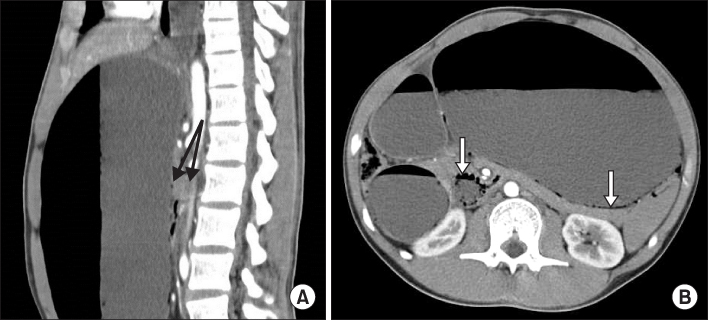

Abdominopelvic CT scans showed marked gastric distention and proximal duodenal dilatation with compression of the third segment between SMA and abdominal aorta. The SMA angle to the aorta is normally 45° (range, 38° to 56°), whereas in SMA syndrome, the SMA angle is decreased to 6° to 25° [8]. The patient's aortomesenteric angle was decreased to 12°. Also, there were thin linear mural airs in the walls of the stomach and duodenum (Fig. 1). These findings were consistent with SMA syndrome. Based on the CT scans and his clinical symptoms, the patient was diagnosed as having gastric emphysema related with SMA syndrome. For gastric decompression, nasogastric tube was inserted and intravenous hydration was promptly started. Total parenteral nutrition was started from the day of admission, and he was observed closely in the intensive care unit. The intravenous broad spectrum antibiotics was added and to rule out the emphysematous gastritis, blood and gastric fluid were cultured.

The characteristic radiographic features of gastric emphysema are thin, linear streaks of air along the border of the stomach [16]. CT scans help to confirm this linear distribution of intramural air [17]. However, unlike gastric emphysema, emphysematous gastritis can demonstrate mottled mucosal fold thickening with irregular collections of gas within the stomach wall [17]. In our case, abdominopelvic CT scans showed thin linear air accumulations in the walls of the stomach and duodenum. They also revealed marked gastric distention and proximal duodenal dilatation with compression of the third segment between the SMA and abdominal aorta.

Fig. 1

Contrast enhanced abdominal computed tomography scan. It shows severe gastric distention with air-fluid level and fluid-filled duodenal dilatation. Extrinsic compression of third segment of duodenum between superior mesenteric artery (SMA) and abdominal aorta and a narrow aortomesenteric angle to 12° (A, black arrows) are suggestive of SMA syndrome. Multiple thin linear air densities within the distended gastric wall is suggestive of gastric emphysema (B, white arrow).

Fig. 1 Contrast enhanced abdominal computed tomography scan. It shows severe gastric distention with air-fluid level and fluid-filled duodenal dilatation. Extrinsic compression of third segment of duodenum between superior mesenteric artery (SMA) and abdominal aorta and a narrow aortomesenteric angle to 12° (A, black arrows) are suggestive of SMA syndrome. Multiple thin linear air densities within the distended gastric wall is suggestive of gastric emphysema (B, white arrow).